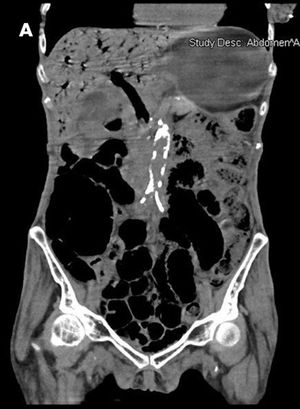

A 70-year-old woman with poorly controlled type 2 diabetes mellitus (hemoglobin A1c, 12.5%) and hypertension was brought to the emergency department for evaluation of abdominal pain and loose bowel movements.